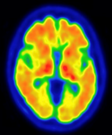

日本メジフィジックス株式会社 様

画像提供:東京都健康長寿医療センター 認知症未来社会創造センター 副センター長 石井 賢二 先生 提供

アミロイドβプラークが溜まっていない場合(陰性)

認知症の原因がアルツハイマー病である可能性が低いと考えられます。